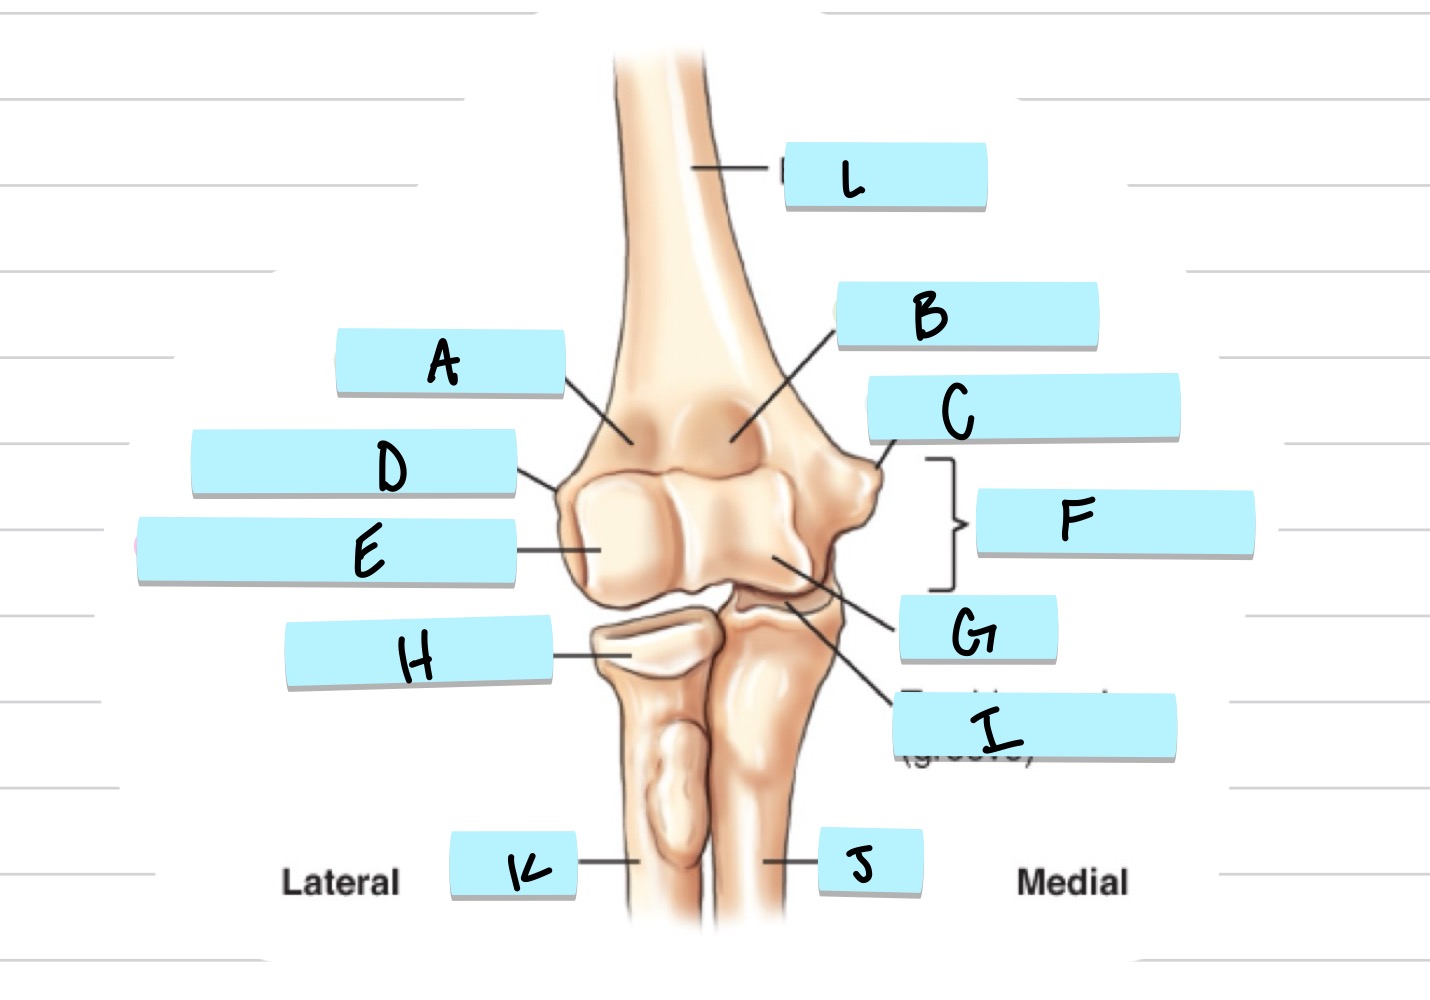

<p>What is A?</p>

What is A?

olecranon process

New cards

<p>what is B?</p>

what is B?

trochlear notch

37

<p>what is C?</p>

what is C?

coronoid process

38

<p>what is D?</p>

what is D?

radial notch

radial fossa

coronoid fossa